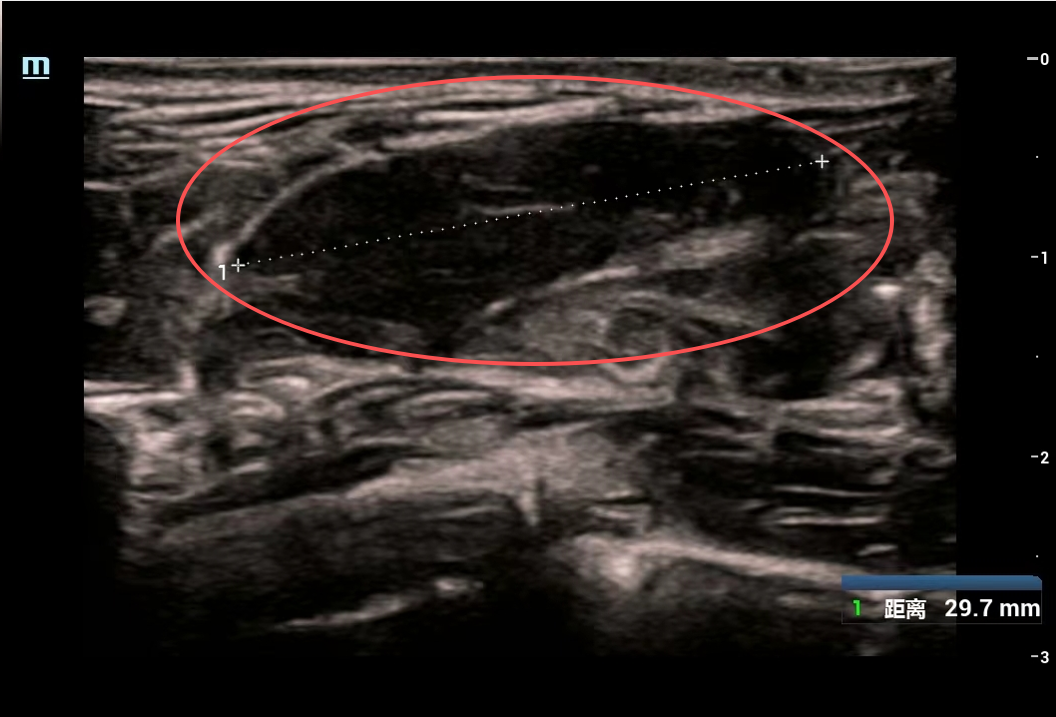

美美的检查结果让医生与家属心头一紧:她的双侧乳房内竟散落84个大小不一的肿块,其中最大一个达6厘米×5厘米,如同鹅蛋大小。

虽然彩超乳腺分级标准为3级,穿刺活检显示为良性结节,但如此庞大的数量和体积的肿块,已严重威胁乳腺健康,需手术处理。

面对84个肿块这一罕见情况,医生迅速启动多学科会诊,为美美制定个体化手术方案以兼顾清除效果与乳腺保护,经手术精准切除72个较大肿块;剩余12个小结节,在术中超声引导下,行乳房肿物低温等离子体消融术。